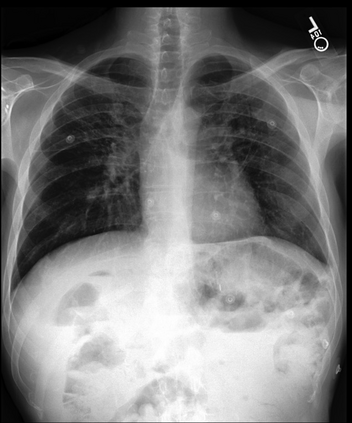

To address these issues, we propose a novel Adaptive patch-word Matching (AdaMatch) model to correlate chest X-ray (CXR) image regions with words in medical reports and apply it to CXR-report generation to provide explainability for the generation process. AdaMatch exploits the fine-grained relation between adaptive patches and words to provide explanations of specific image regions with corresponding words. To capture the abnormal regions of varying sizes and positions, we introduce the Adaptive Patch extraction (AdaPatch) module to acquire the adaptive patches for these regions adaptively. In order to provide explicit explainability for CXR-report generation task, we propose an AdaMatch-based bidirectional large language model for Cyclic CXR-report generation (AdaMatch-Cyclic). It employs the AdaMatch to obtain the keywords for CXR images and `keypatches' for medical reports as hints to guide CXR-report generation. Extensive experiments on two publicly available CXR datasets prove the effectiveness of our method and its superior performance to existing methods.